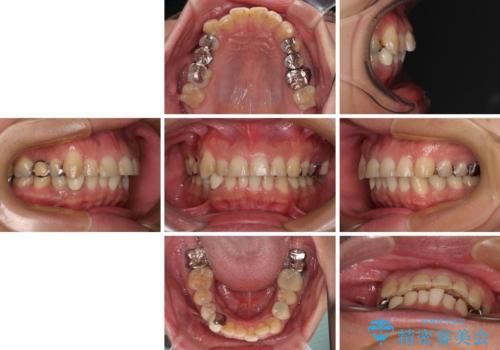

- 近医にて下顎奥歯の抜歯が必要と言われたとのことで来院された患者様です。

診察の結果、奥歯は左右ともに抜歯が必要な状態でした。

他の銀歯も気になっており、セラミックにしたいとの要望があり、詳しくお話をすると、デコボコの歯ならびも整えたいとのことでした。

抜歯が必要な歯は事前に抜歯をし、その後ワイヤー装置にて歯列矯正を行い、途中でインプラントを埋入し、オールセラミッククラウンにて補綴治療を行うこととしました。